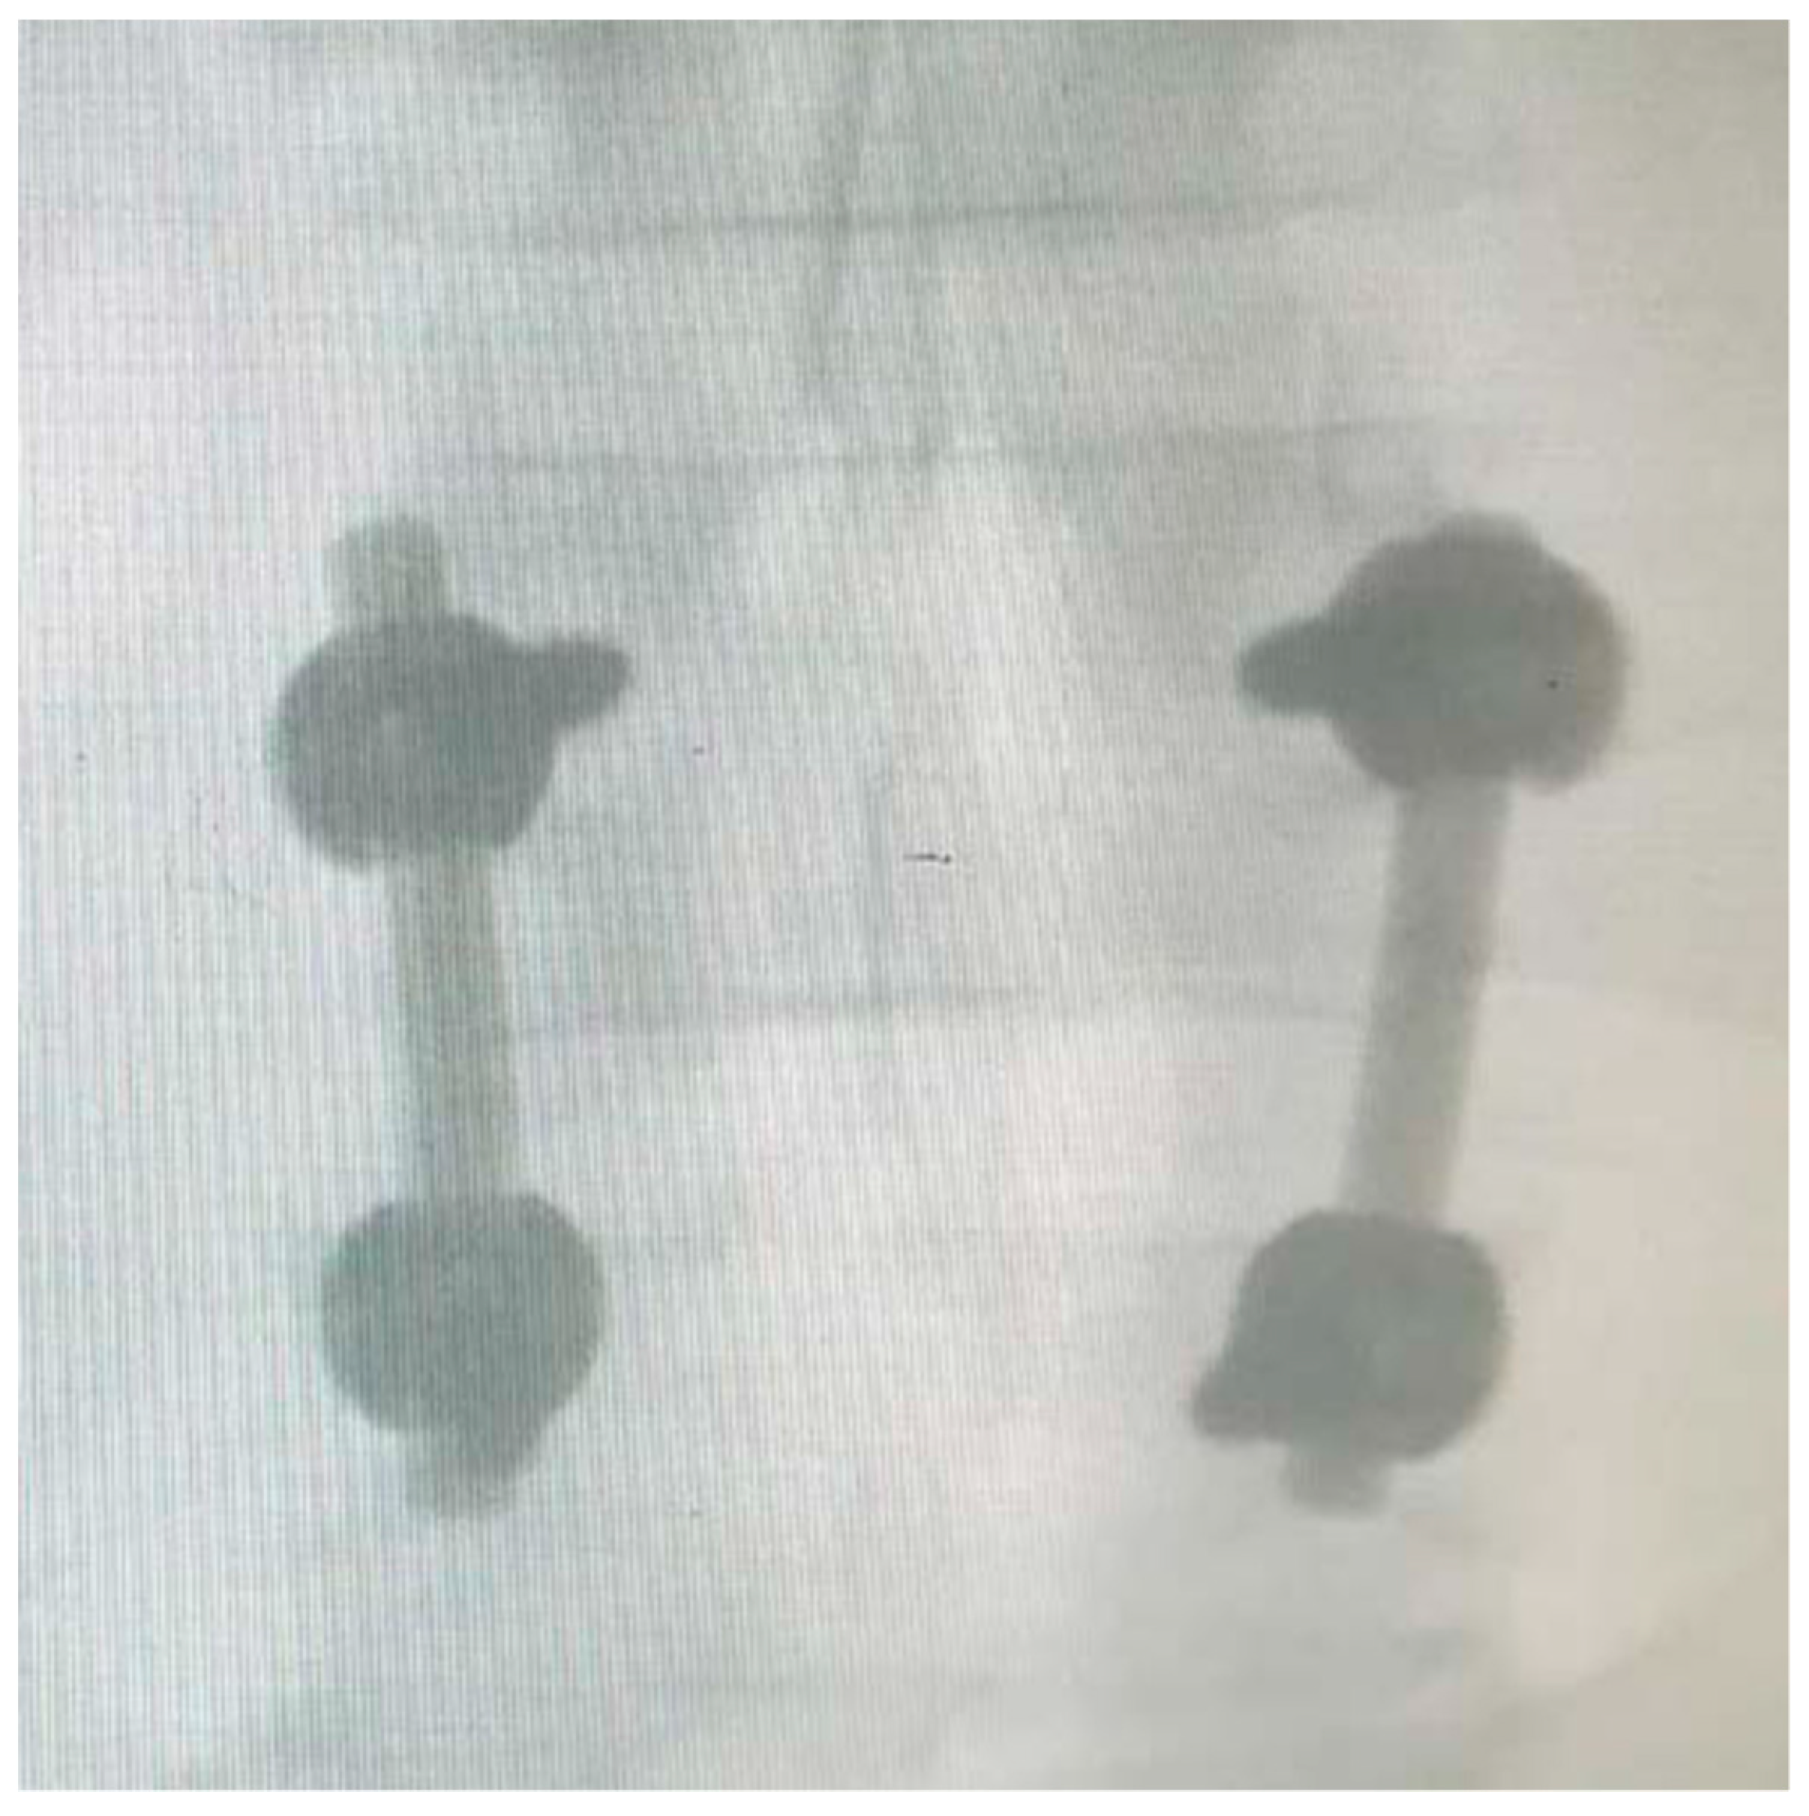

Figure 6, Figure 7, Figure 8 and Figure 9 show examples of pre- and post-operative X-ray shots.

Figure 7. Post-operative coronal X-ray check—patient code: 2ATL3L4L5110.

Figure 9. Post-operative coronal X-ray check—patient code: 5BML4L501.